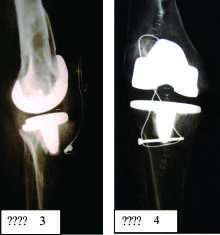

Ծնկոսկրի սեփական կապանի պատռվածքները վերակնգնվեցին չներծծվող թելերով և կապանը բեռնաթափելու նպատակով դրվեց ութաձև մետաղական ամրալար՝ մեծ ոլոքի թմբկությունից դեպի ծնկոսկր: Հյուսվածքները շերտ առ շերտ վերականգնվեցին, վերքը դրենավորվեց և Բետադինի լուծույթով դրվեց ասեպտիկ վիրակապ (նկար 3 և 4):

Վիրահատությունը տևեց 2 ժամ 45 րոպե: Վիրահատության ժամանակ և հետվիրահատական շրջանում հիվանդը ստացել է ադեկվատ հակաբիոտիկային և ինֆուզիոն թերապիա, ցավազրկողներ, էրիթրոցիտային զանգված: